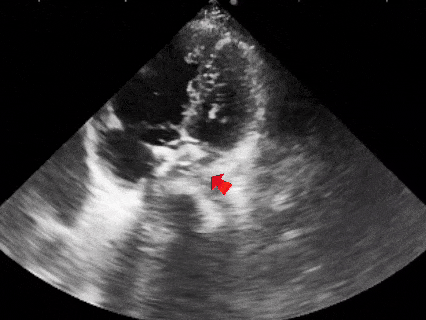

超声下观察封堵器,左右盘面在房间隔两侧,彩超下无残余分流

多普勒观察封堵器成型后无残余分流

多普勒观察无残余分流